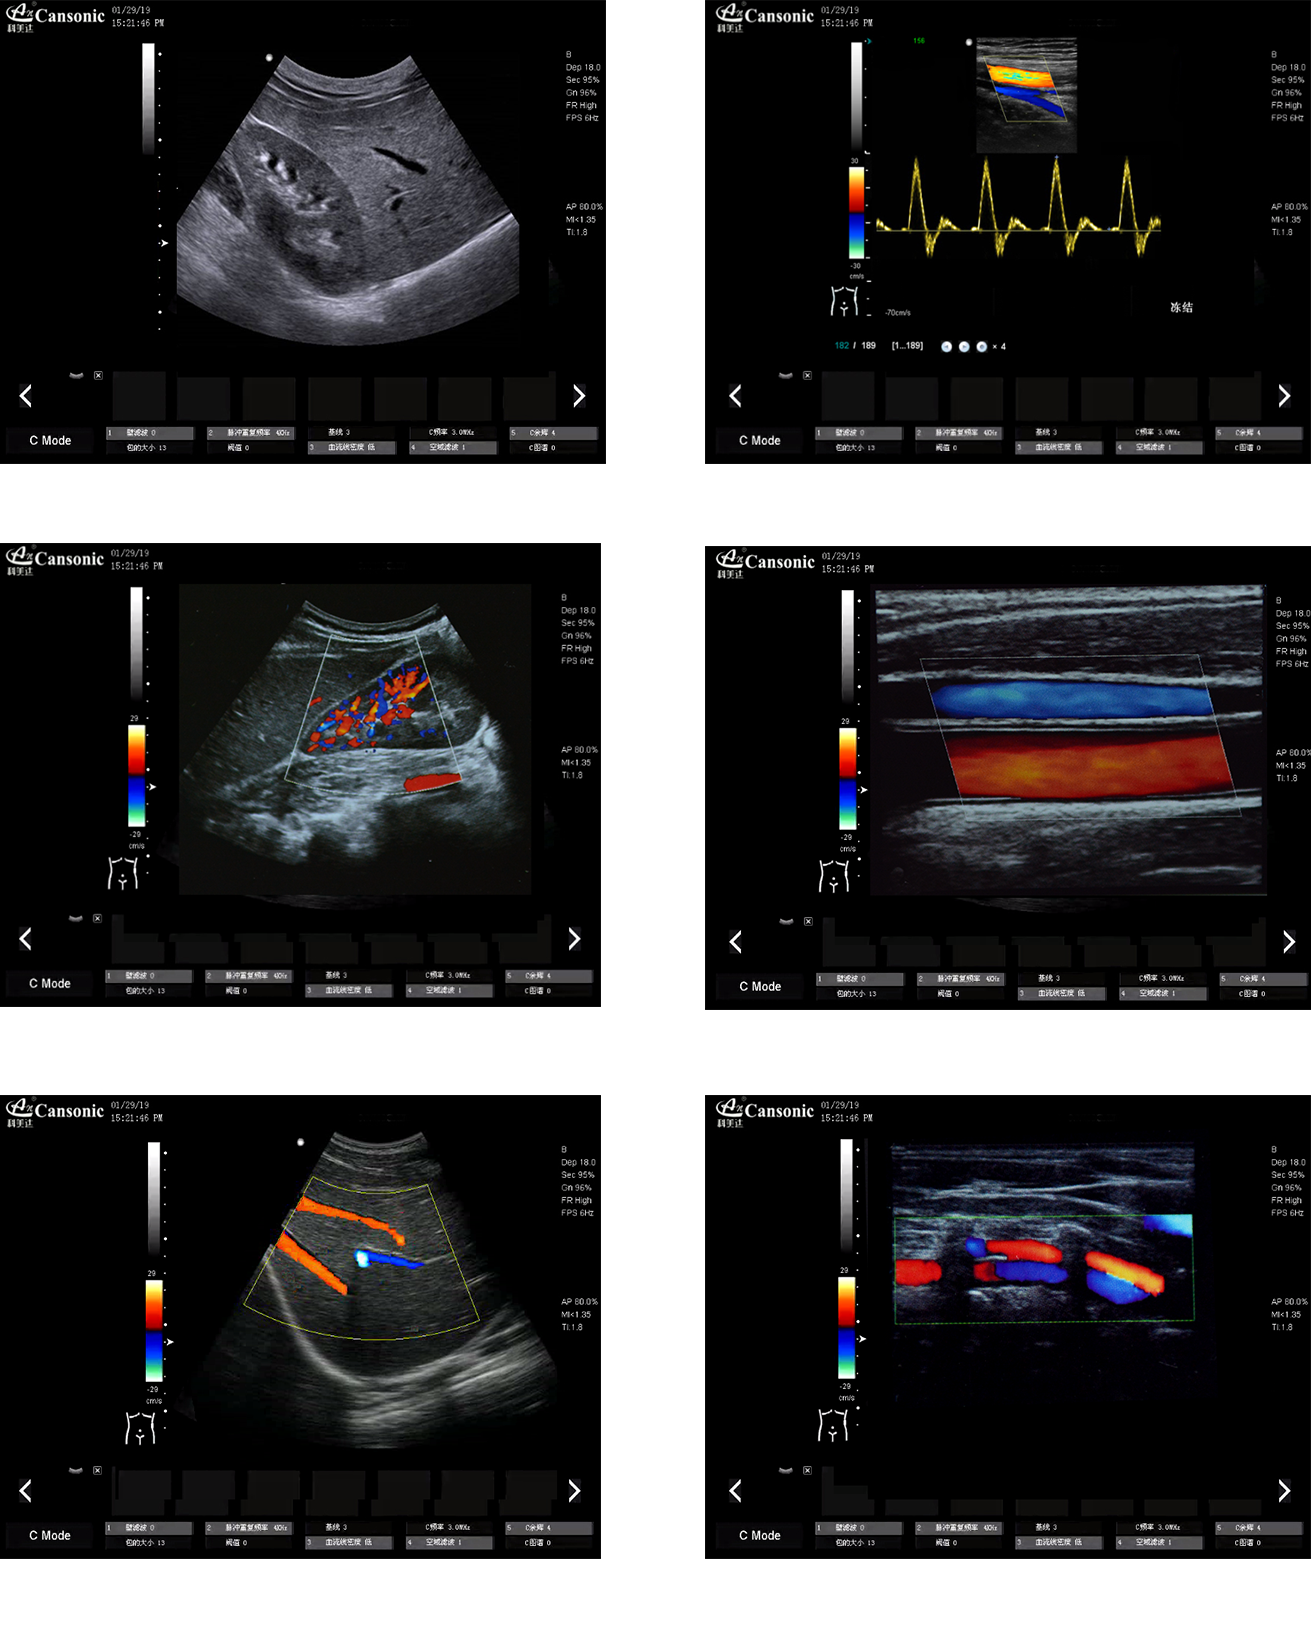

热博RB88K22图像实例